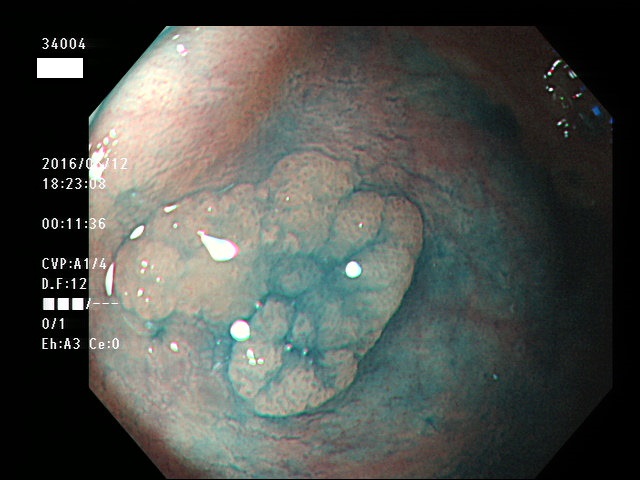

上記100名より抽出した平坦・陥凹型腺腫(=癌化の危険が高いが見落としやすい病変)の内視鏡写真